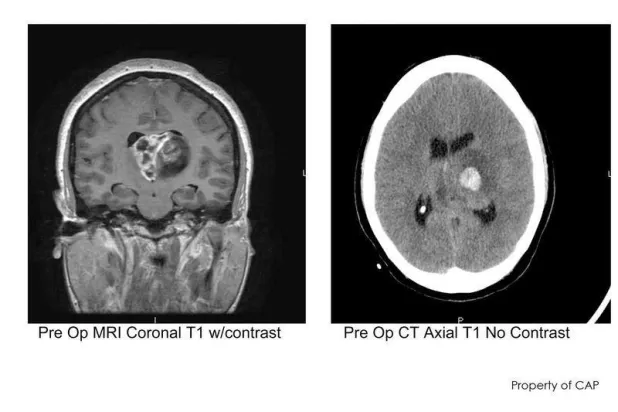

خلصت تجربة سريرية عالمية إلى أن أول لقاح في العالم لعلاج أورام الدماغ السرطانية المميتة يمكن أن يمنح المرضى سنوات من العمر الإضافي. وقال طبيب كبير في هئية الخدمات الصحية الوطنية في بريطانيا، كان أحد العلماء الرئيسيين في التجربة، إن الأدلة أظهرت أن «DCVax» قد أدى إلى تعزيز البقاء على قيد الحياة بطريقة «مذهلة» للمرضى، وفقاً لصحيفة «الغارديان». يمكن لهذا الاختراق أن يفيد 2500 شخص سنوياً في المملكة المتحدة تم تشخيص إصابتهم بالورم الأرومي الدبقي، وهو الشكل الأكثر شيوعاً لسرطان الدماغ، وأكثره عدوانية.

على الرغم من أن أورام المخ نادرة نسبياً، فإنه يتم تشخيص إصابة نحو 12 ألف شخص بالمرض في المملكة المتحدة كل عام، بما في ذلك المشاهير، مثل تينور راسل واتسون، والموسيقي والممثل مارتن كيمب، والمغني المطلوب توم باركر. * ما الأعراض المحتملة للمرض؟ من المهم أولاً معرفة أن هذه العلامات وحدها لا تعني تلقائياً أنك مصاب بسرطان في الدماغ، ولكن إذا كنت قلقاً، فعليك استشارة طبيبك، وفقاً لتقرير لصحيفة «إندبندنت». - النوبات: إذا كنت تعاني نوبات متكررة أو مفاجئة، فيجب عليك استشارة اختصاصي؛ حيث سيطلب إجراء مسح عاجل للدماغ. - ضعف في الوجه أو الذراع أو الساق، على جانب واحد من الجسم: قد يحدث هذا الضعف فجأة، مثل الس

عندما تصبح الخلايا سرطانية، فإنها تخضع لسلسلة من التغييرات الكهربية الحيوية.